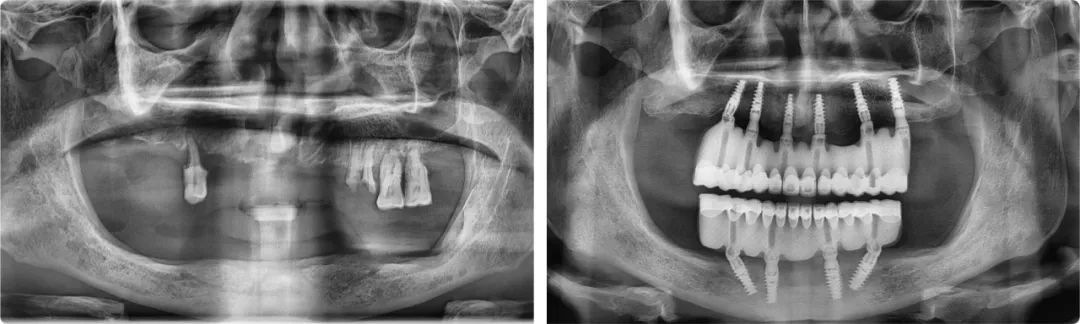

2019年12月31日,拔牙、植入10顆種植體、取模、戴牙(臨時修復體)、調整,當所有治療程序全部完成,時針已滑過零點。這次跨年手術是王旭東完成的第一例全口種植修復治療,也是陳醫生過得最開心的一個元旦。新的一年,他終于可以正常吃飯、說話,無所顧忌地大笑了。

王旭東首例全口種植案例術前術后全景片

幾年來,陳醫生除了定期復查,還介紹了不少朋友前來找“老王”,今年十月,他又陪老伴來做了半口種植。看到王旭東工作繁忙,他還為王旭東把脈看診,教給他中醫養生知識,叮囑他注意休息。